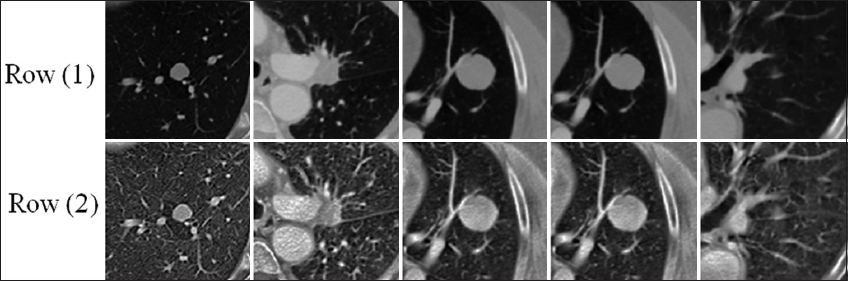

Our preprocessing techniques were used to enhance the feature of the images, which in turn improve the performance of the detection and classification, by enhancing the contrast of specific ranges after adjusting the intensity levels according to local histograms [26], this stage involved the contrast limited adaptive histogram equalization (CLAHE) algorithm as shown in Fig. 5, which executed to enhance the contrast of each input image.

thumblarge

Fig. 5. Demonstrates the differences between the original images row (1) and the same images after applying contrast-limited adaptive histogram equalization row (2).